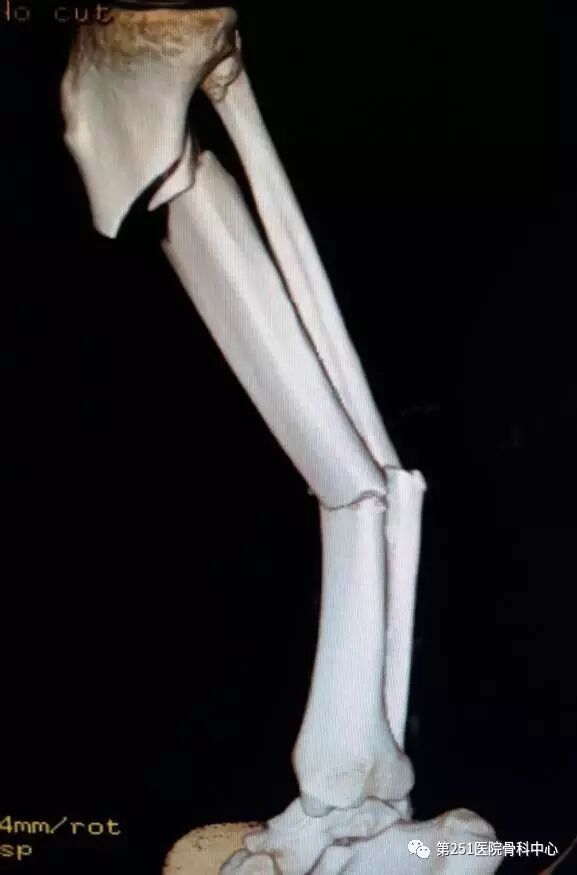

病例1:男性,40岁,车祸伤,胫腓骨多段骨折。